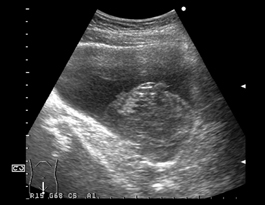

膀胱内に不整な内部エコーの腫瘍が映っている。膀胱に充分尿を溜め、体位を変えて移動が確認できれば腫瘍とは鑑別ができる。血腫は起源が膀胱とは限らず、腎盂など尿路上部からの大量出血でも形成される。 |